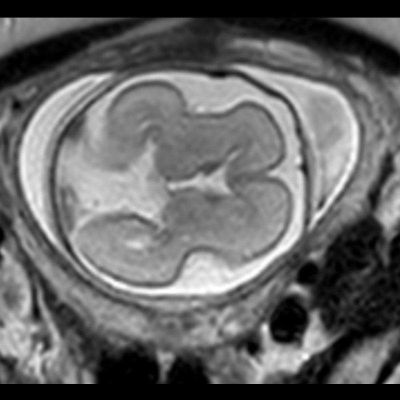

- A) USG incelemede serebral kortikal yapılar düzleşmiş (ok), gyrus sayısı azalmıştır (ok). Kalın ve ekojenik korteks mevcut olup korteks -beyaz cevher ayrımı silik görünümdedir. Posterior fossada ekstraaksiyel BOS mesafesi artmış görünümdedir (ok).

- B) Aksiyel ve sagittal T2A görüntülerde gyrus ve sulkuslarda azalma mevcut olup korteks kalınlaşmış görünümde ve operkulizasyon ayırt edilememiştir. Korteks beyaz cevher ayrımı zor seçilmektedir (ok) Ekstraaksiyel BOS mesafesi artmış görünümdedir (ok). Yapılan ölçümlerde; tegmentovermian açı :8 derece (ok) serebellar vermis boyutları kraniokaudal: 16 mm, aksiyel: 5,5×8,5 mm (ok) ölçülmüş olup BPD:27w ile uyumlu olan fetüste haftasıyla uygun olarak değerlendirilmiştir.

- Gri/beyaz cevher oranı beyaz cevher aleyhine azalmıştır.

- Operkulizasyon yokluğuna bağlı sylvian fissürün açık görünümü ve vertikal yerleşimi karakteristik bir bulgudur. Serebral yapılar; sığ ve vertikal yerleşimli sylvian fissür sebebiyle “8” görünümündedir. Ancak bu görünümün 26. gestasyonel haftaya kadar normal olduğu akılda tutulmalıdır.

- İnsula açıkta olup klastrum ve eksternal kapsül bulunmayabilir. Beynin gross görünümü fetüste sulkusların oluşmaya başladığı 20. gestasyonel haftayla benzer görünümdedir.